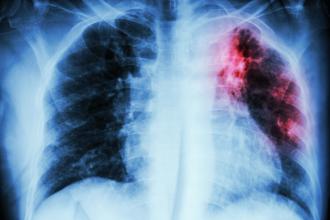

World Tuberculosis Day, recognized on 24 March of each year, raises public awareness about tuberculosis (TB). The global TB epidemic causes several million deaths per year, mostly in the developing world where HIV rates are also at epidemic levels.

Although Canada is considered a low incidence TB country, certain populations remain at increased risk, notably Canadian-born Aboriginals. Recent national data show that the greatest proportion of Canadian-born Aboriginal TB cases were in the Prairie Provinces and the Territories.